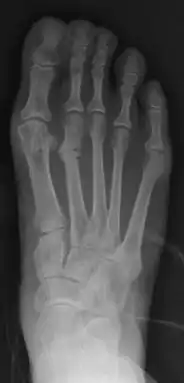

Fig. 8a. Painful hallux valgus and metatarsus primus varus deformity recurrence of left foot after osteotomy surgery